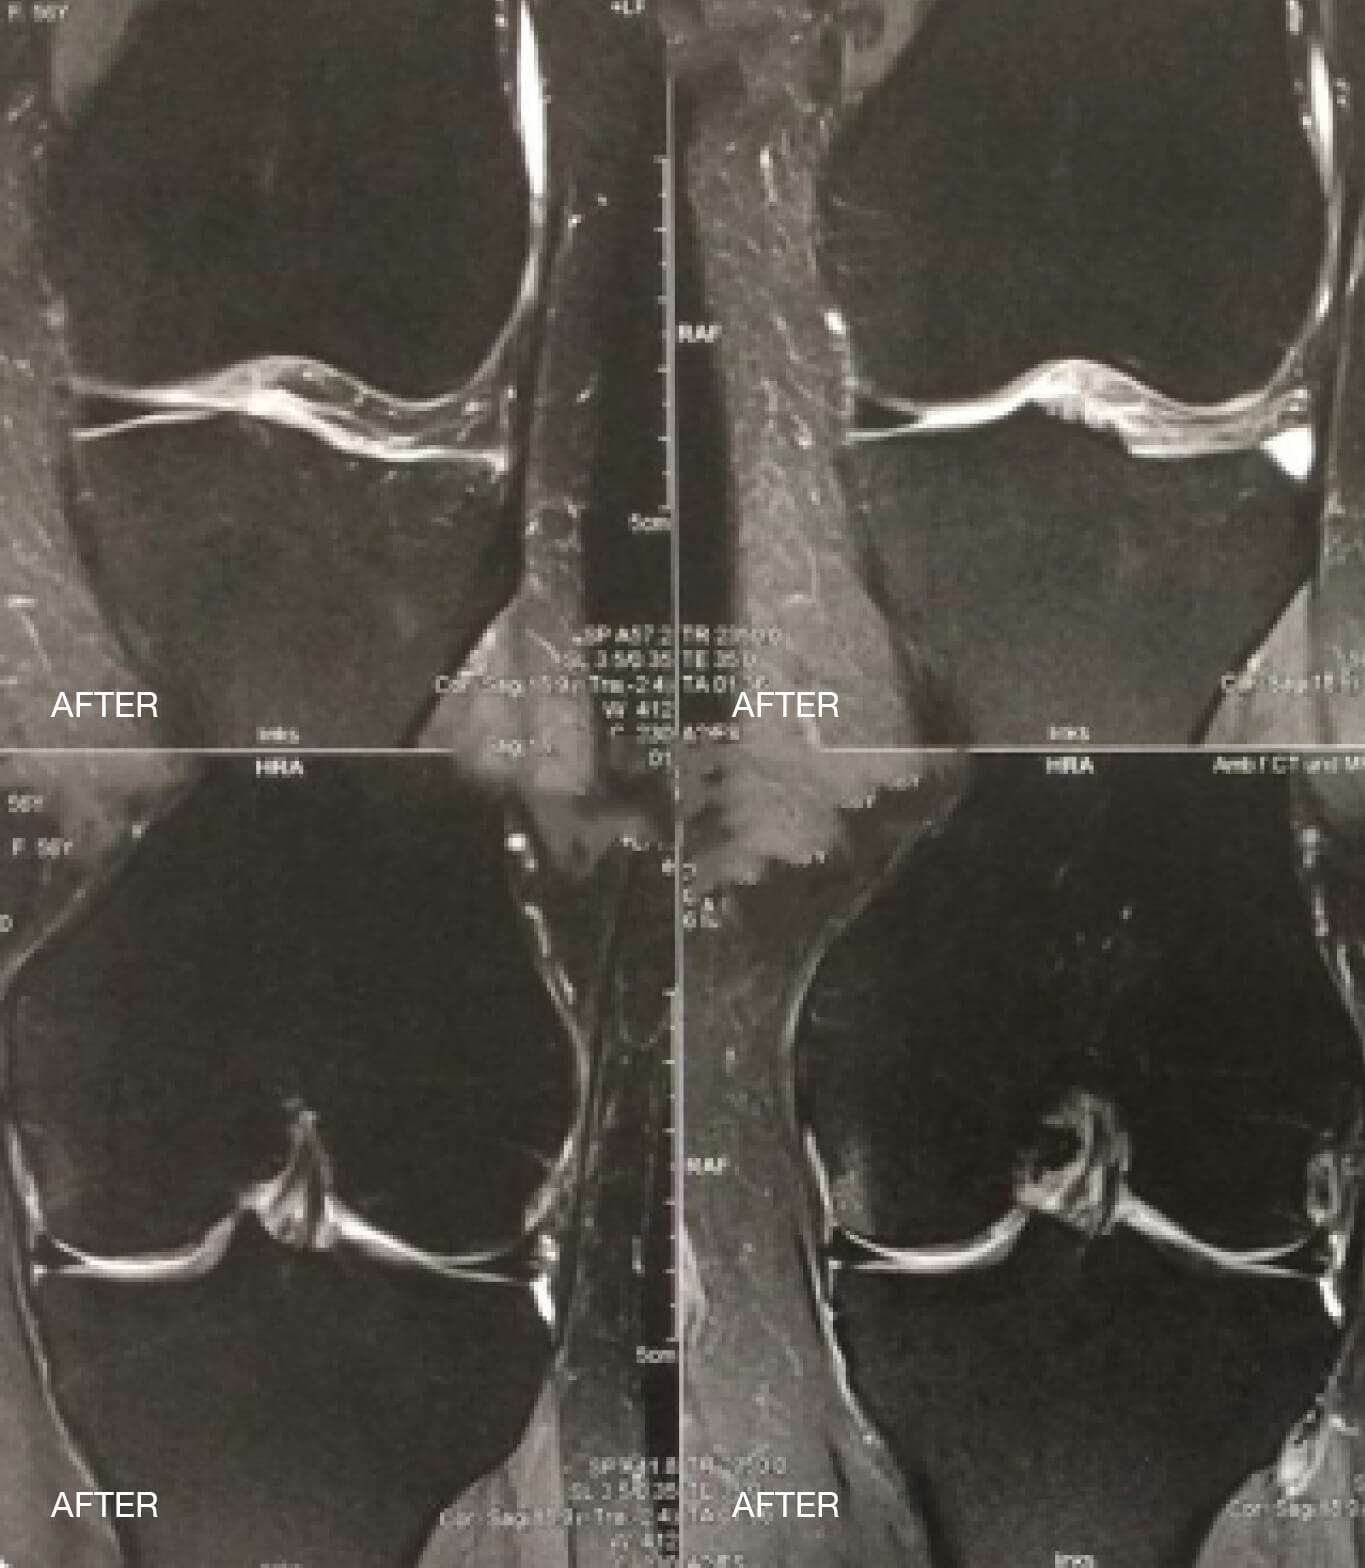

Οι ακόλουθες εικόνες απεικονίζουν ένα οίδημα μυελού των οστών στην άρθρωση του γόνατος πριν και μετά τη θεραπεία papimi. Η θεραπεία ήταν επιτυχής μετά από μόλις 10 συνεδρίες.

Μετά το